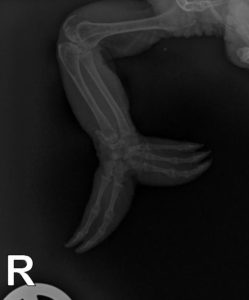

Röntgenbild von Arm und Hand eines Chamäleons

Beim Tierarzt werden Hände und Füße eingehend untersucht. Die Wunden werden gereinigt, desinfiziert und versorgt. Von infizierten Wunden werden Tupfer für Mikrobiologie und Resistenztest entnommen. Bei fortgeschrittenen Fällen können Röntgen-Untersuchungen der Gliedmaßen notwendig sein. Ein reptilienkundiger Tierarzt kann spezielle Verbände anlegen, um die Belastung besonders stark entzündeter Hautstellen zu verringern und damit die Abheilung zu beschleunigen. Verbände an Hand- und Fußflächen werden von Chamäleons in der Regel gut toleriert. Sie sollten nicht vom Halter selbst „zusammen gebastelt“ werden. Ein unsachgemäß angelegter Verband kann zusätzliche Druckstellen und die Entstehung weiterer Wunden verursachen, die den Heilungsverlauf negativ beeinträchtigen können. Auch vom Auftragen von Salben ohne vorherige Diagnostik kann nur abgeraten werden.